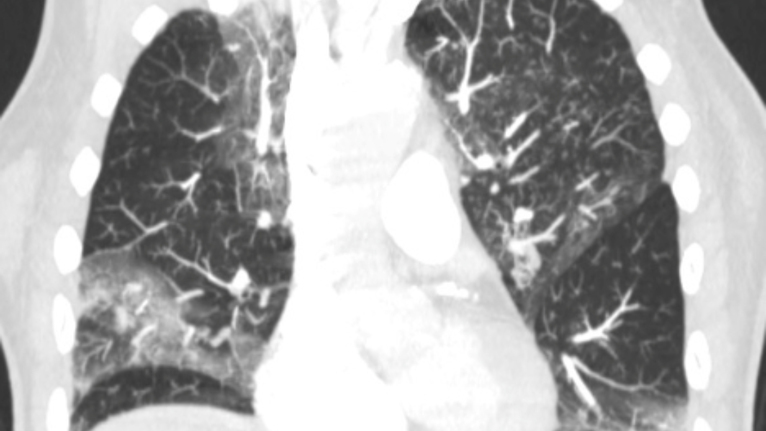

COVID-19 Lung X-Ray - 3 - Lung Damage

Figure 7 - CT chest showing multifocal ground glass opacities from COVID-19 bronchopneumonia.